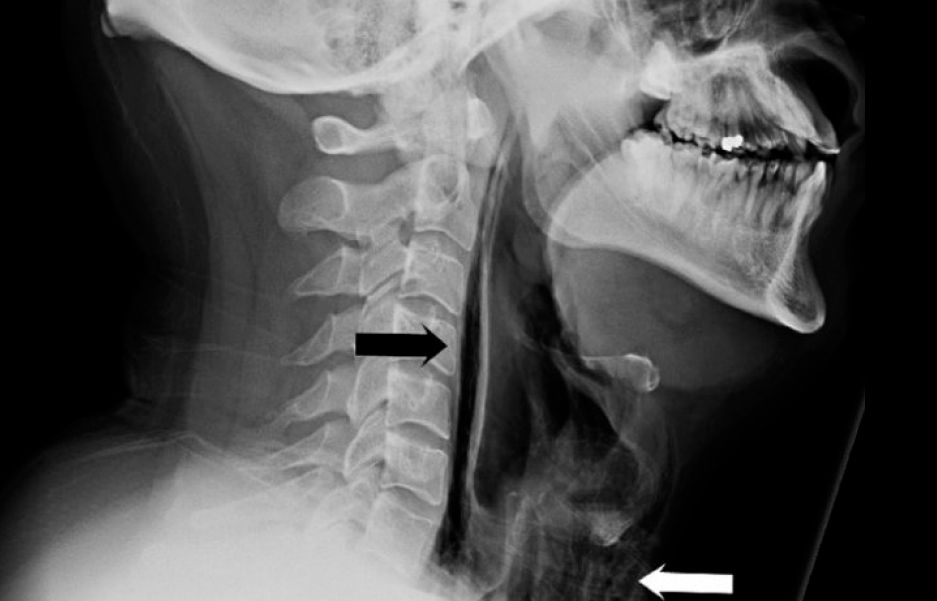

Riss im Rachen

Der Arzt konnte zwar kein Fieber und auch keine Atemnot feststellen, vernahm vom Hals bis zu beiden Seiten des Brustbeines allerdings ein Rasseln im Körper des Patienten. Röntgen- und CT-Bilder zeigten dann einen Riss im Schlund, durch den Luft in Gewebeschichten am Hals vorgedrungen waren, wo normalerweise keine hingehört. Außerdem entdeckten die Mediziner Luft im oberen Bereich des Mittelfellraumes, der vom Zwerchfell aufwärts zwischen den Lungenflügeln Richtung Hals verläuft.